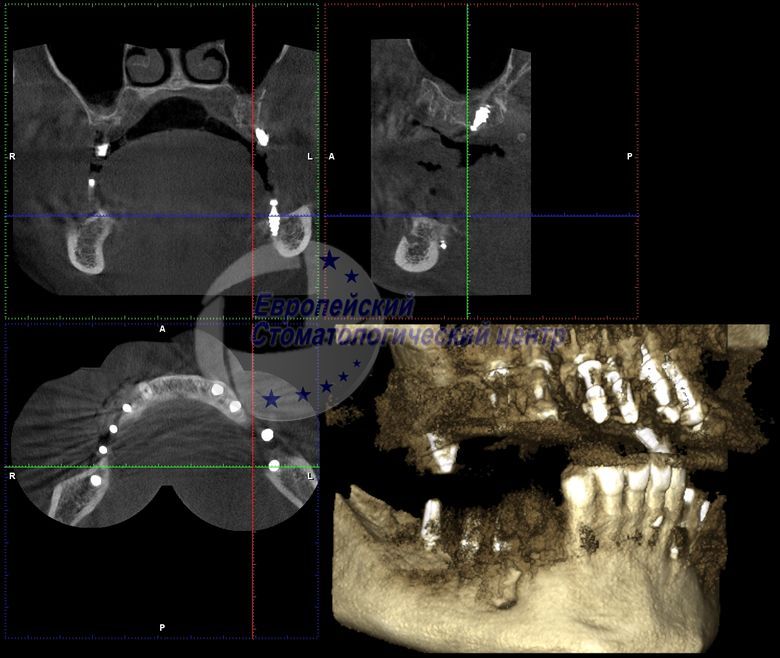

CT one year after surgery